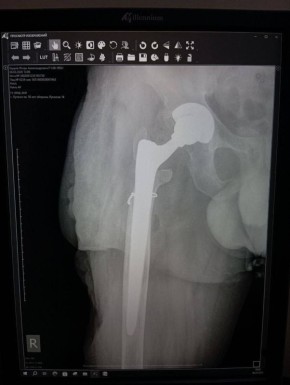

Уникальная операция в Луганской республиканской клинической больнице вернула ветерану специальной военной операции (СВО) возможность ходить без хромоты. Об этом сообщила министр здравоохранения ЛНР Наталия Пащенко. Руководитель Минздрава...

Об этом сообщила министр здравоохранения ЛНР Наталия Пащенко.Руководитель Минздрава рассказала, что борьба сержанта из ЛНР, мужчины 1993 года рождения, длилась три с половиной года. За это время он проходил лечение в десяти госпиталях, в том числе в...

Об этом сообщила министр здравоохранения ЛНР Наталия Пащенко в своем телеграм-канале.Боец ушел на фронт 25 февраля 2022 года, прошел через горнило Херсонщины, а тяжелое ранение получил 28 августа.«Из-за обширных повреждений и многократных операций...

Об этом сообщила министр здравоохранения ЛНР Наталия Пащенко.Боец ушел на фронт 25 февраля 2022 года, прошел через горнило Херсонщины, а тяжелое ранение получил 28 августа.«Три с половиной года борьбы. Десять госпиталей. И одна операция, которая...